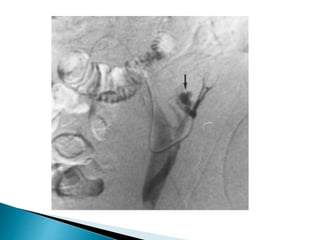

1. Urinary leak

2. Ureteral necrosis

3. Ureteral obstruction

4. Torsion

URINARY LEAK